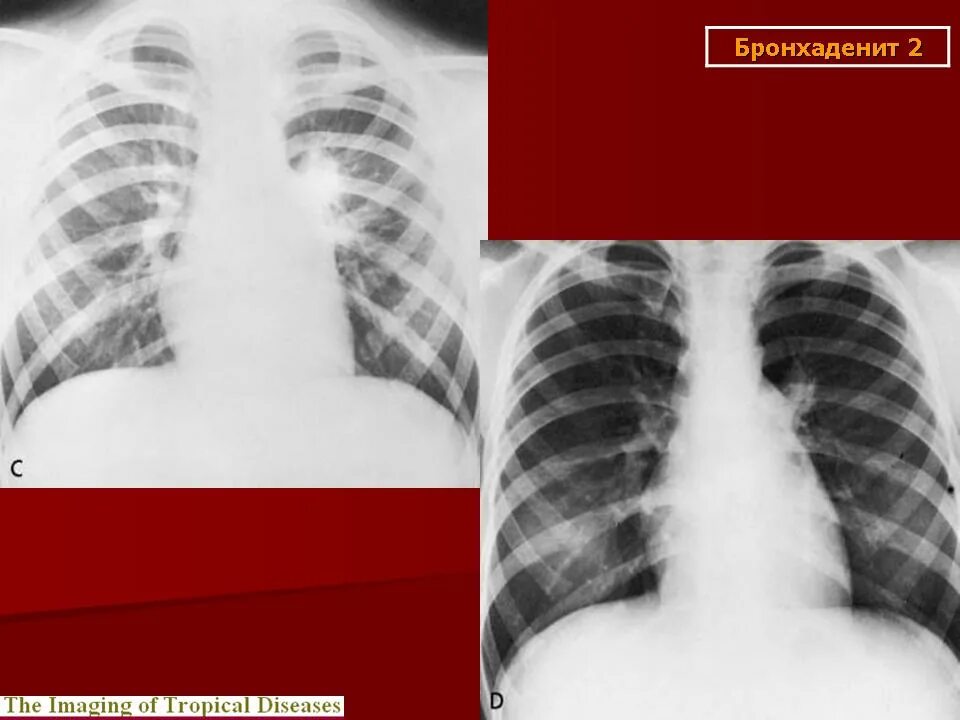

Увеличение внутригрудных лимфатических узлов